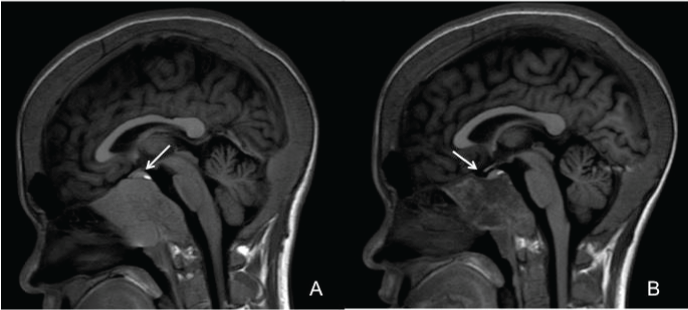

| Figure 2: MRI of the orbit and brain. (A) Sagittal T1-weighted showing massive expansion of marrow originating from clivus, obliterating bilateral sphenoid sinuses and pituitary fossa. Pituitary gland is also displaced upward from the tumor-like expansion of marrow (arrow). Enlargement of the diplopic space of calvarium is also depicted. (B) Sagittal T1-weighted showing reduction in the size of tumor-like expansion with visible pituitary fossa (arrow). |